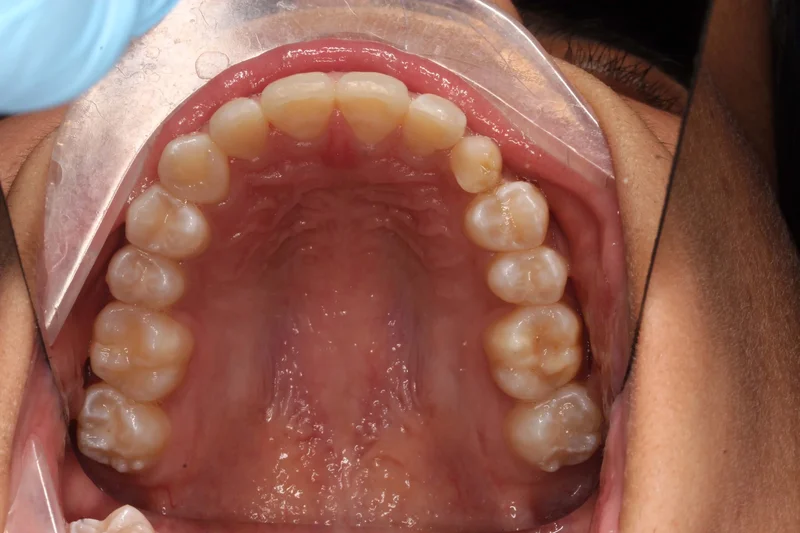

Upper Occlusal

Upper Occlusal - Before Treatment

Before

Upper Occlusal - After Treatment

After